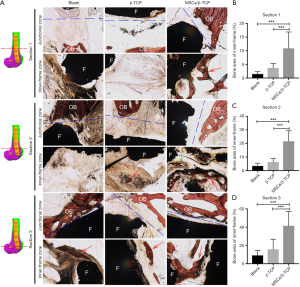

Evaluations of the bone defect repair

All bone defects were detected by X-ray 1, 3, and 6 months after surgery and CT scans 6 and 9 months after surgery. At 9 months after surgery, all animals were sacrificed, and the surgical part of the distal femur was completely removed. Those samples were fixed with paraformaldehyde at room temperature. The samples were then embedded in polymethyl methacrylate and cut into 100-µm thick slices with a diamond band saw (EXAKT300CP, Norderstedt, Germany) followed by polishing down to 50 µm with a plate grinder (EXAKT310, Norderstedt, Germany) for Van Gieson’s picro-fuchsin staining. Briefly, the slides were sequentially treated with 0.1% formic acid for 3 minutes and 20% methanol for 2 hours before being stained with Stevenel’s blue at 60 °C and Van Gieson’s picro-fuchsin at room temperature. The ratios of the new bone area in the frame to the whole slice area between different groups according to the staining using Image-Pro Plus 6.0 were compared.

Histological analysis was performed to evaluate the new bone growth inside the frame and the osseointegration between the frame and the offside bone. At the junction of the frame and the contralateral bone, good osseointegration was seen in each group’s distal section, but osseointegration in the proximal and middle sections was poor. In the blank group, fibrous tissue predominated inside the frame, and only a small amount of new bone was formed. In the β-TCP–filled group, the β-TCP particles were almost completely degraded and substituted mainly by fibrous tissue at each section with a small amount of new bone. In the MSCs/β-TCP–filled group, the material was completely degraded, and new bone formation with normal trabecular structure was seen in each section. Further, a regenerated Haversian system was also observed (Figure 8A). Quantitative analysis showed that the relative area of new bone was significantly higher in the MSCs/β-TCP–filled group than in the β-TCP implantation group or the blank group at the proximal section (10.8%±6.0% vs. 3.7%±1.7% vs. 1.4%±0.9%, respectively; F=10.953, P<0.01), middle section (21.6%±7.8% vs. 6.3%±2.6% vs. 3.4%±2.1%, respectively; F=24.098, P<0.01), and distal section (41.5%±15.5% vs. 15.8±11.0% vs. 9.1%±5.3%, respectively; F=13.558, P<0.01) (Figure 8B,C,D).

To observe the osteogenesis effect inside the frame, we performed segmented slices of the repaired frame. A better bone construction effect within the frame could be seen at each section in the MSCs/β-TCP–filled group, with the new trabecular bone tightly integrated with the frame wall and the Harval system under reconstruction, which suggests that the new bone has good plasticity. Generally, the new bone area at the distal section accounts for a relatively large proportion of the area. This characteristic may be due to the larger contact area between the distal part and the contralateral normal bone, which results in a more complete local osteogenesis environment. Studies have shown that the degradation cycle of porous β-TCP is between 6 to 18 months. In this study, the porous β-TCP with a diameter of 1–3 mm implanted in the defect region was almost degraded by 9 months after surgery, consistent with previous reports.

Interestingly, in the pure β-TCP–filled group, a small new bone island appeared at the center of the filling area, suggesting that the new bone formation mode mediated by porous materials did not completely depend on the gradual replacement from the surrounding normal bone to the material pores. The ossification process may also occur independently inside the porous material, possibly through the penetrated bone marrow. Although the CT results indicated tissue ingrowth in the three groups, the amount of new bone in the blank group and β-TCP–the filled group was very limited and mainly manifested as fibrous scar tissue. Accordingly, the filler’s osteogenic capacity significantly affected the long-term osteogenic effect, and the MSCs/β-TCP prepared by SECCS exhibited better osteogenic performance in this defect model.